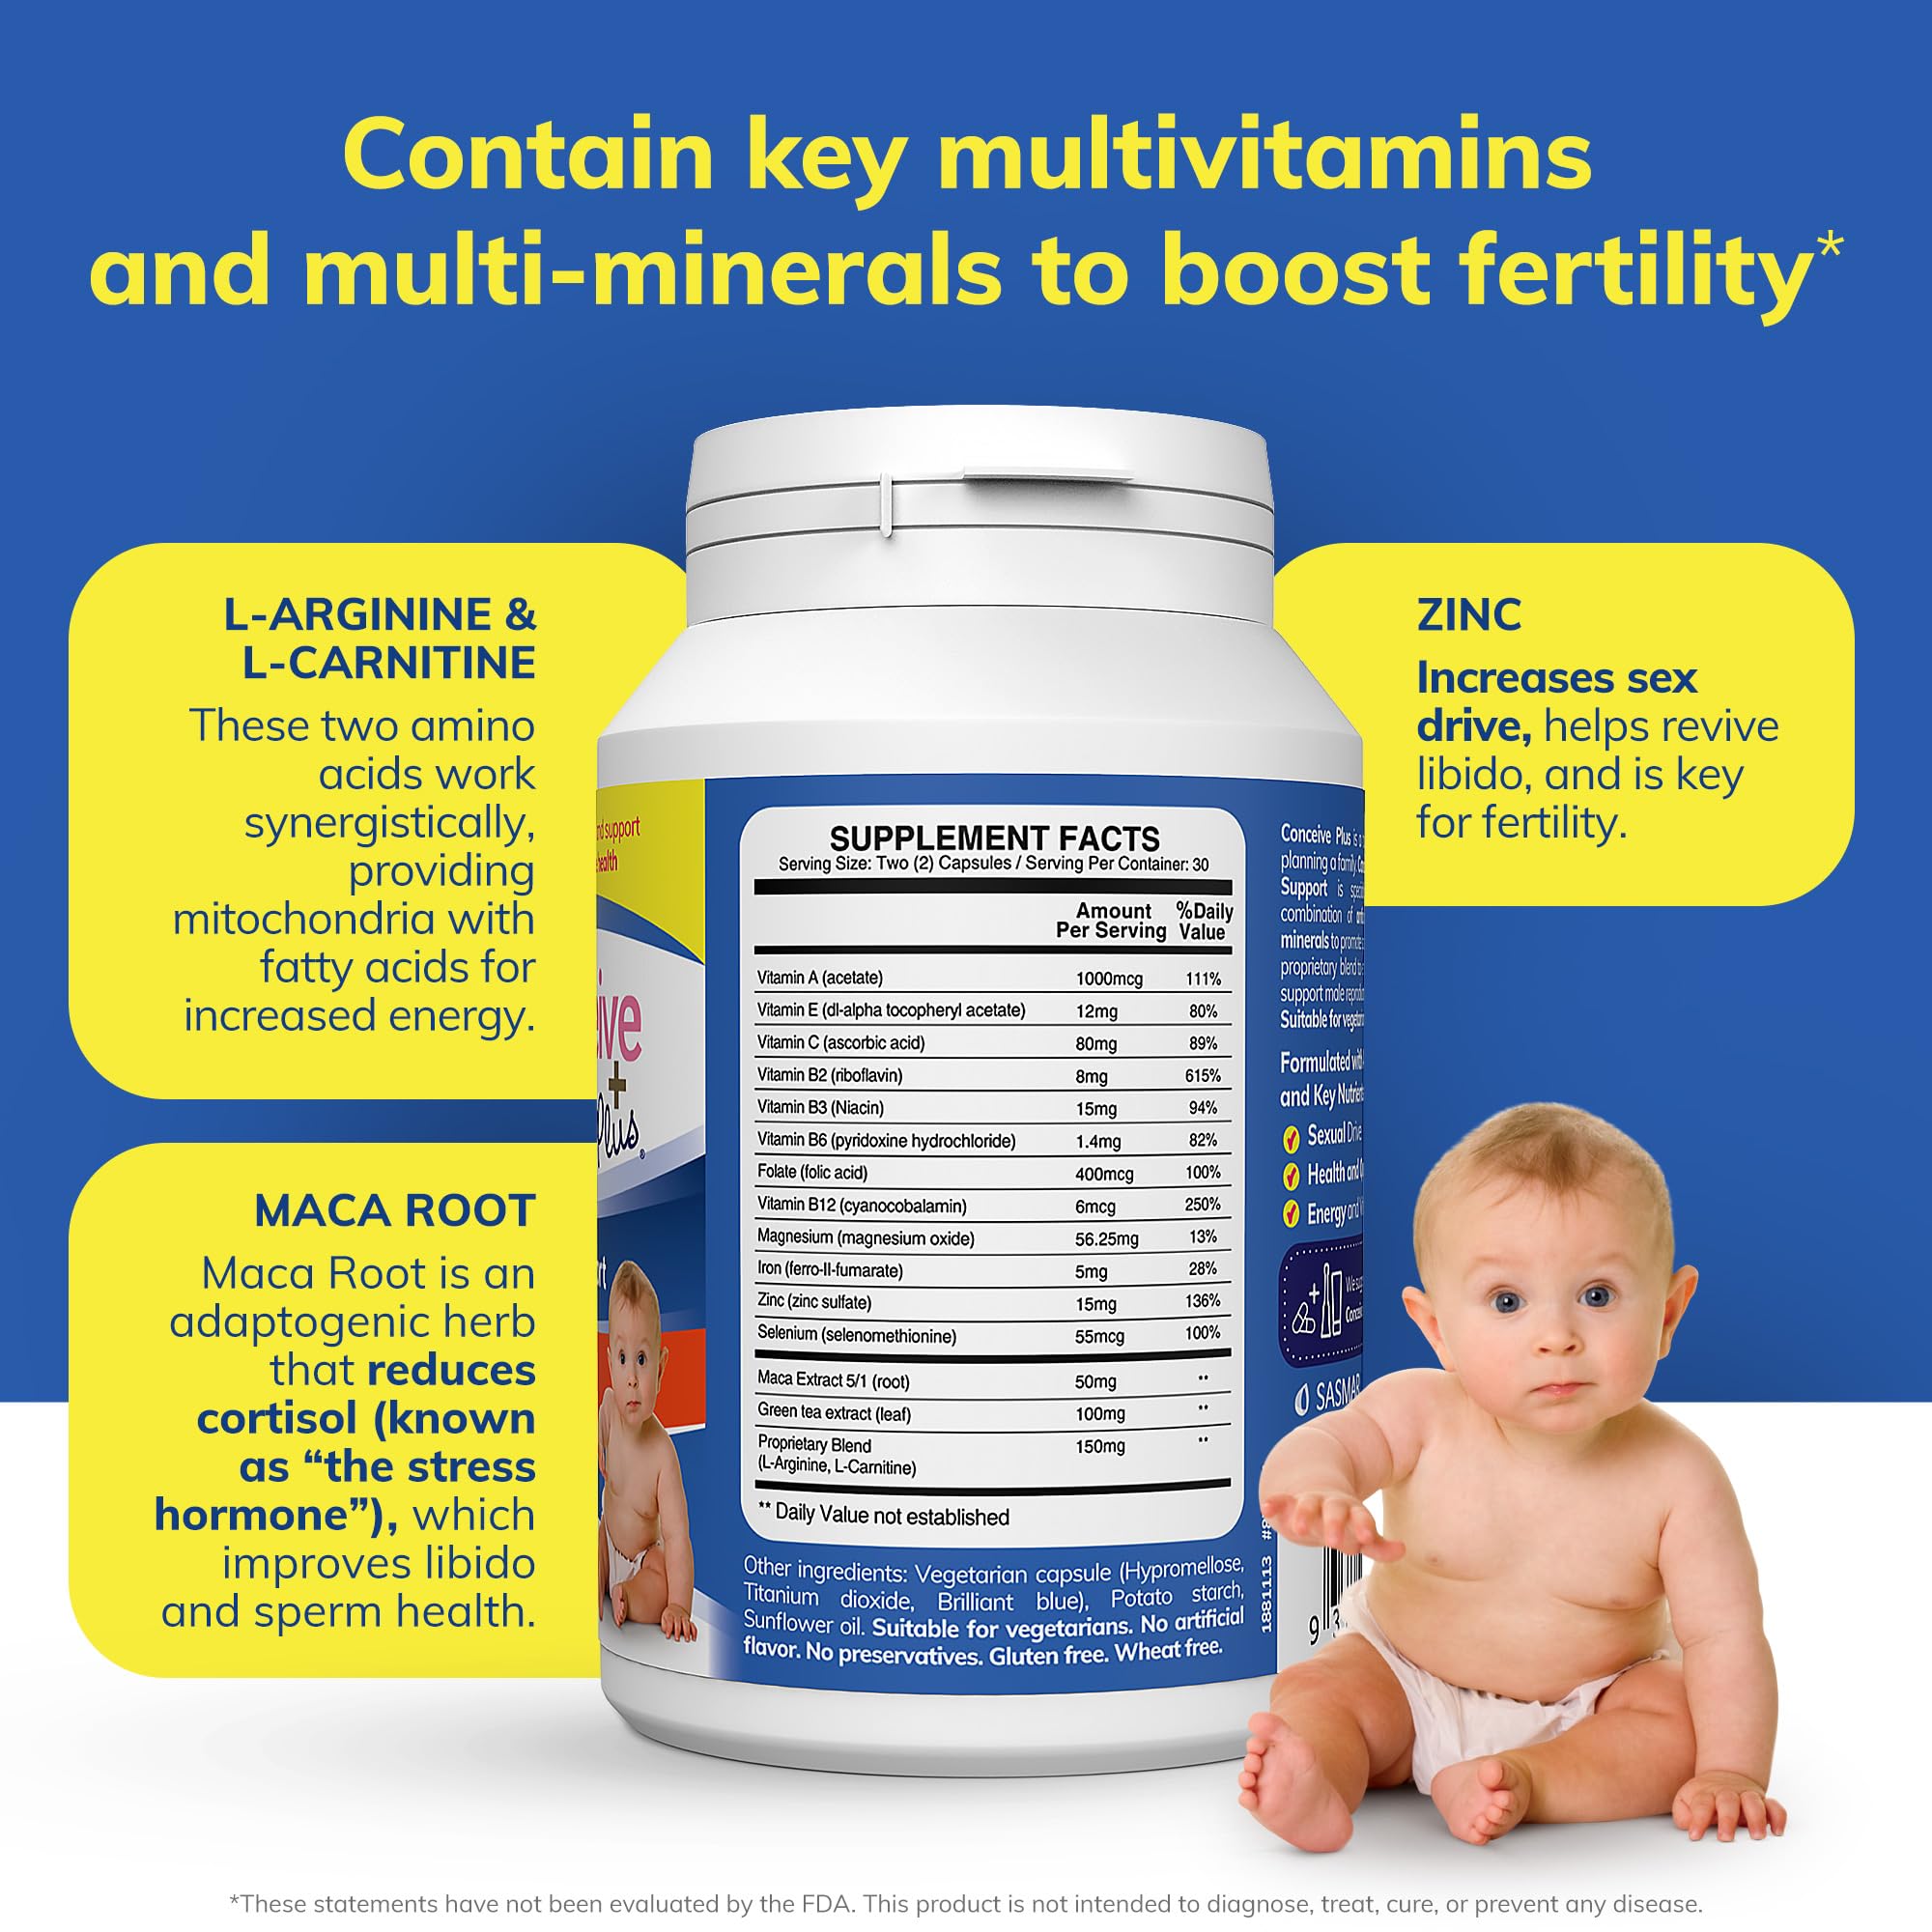

Conceive Plus Fertility Supplements for Men, Male Fertility Booster Prenatal – Optimal Sperm Count & Motility – Maca, L-Arginine, Zinc, Folate Folic Acid & Magnesium – 60 Vegetarian Soft Blue Capsules

- Advanced Men Fertility Supplements: Designed to boost male fertility, our supplement supports natural conception. Carefully formulated with all essential vitamins and nutrients that aid in improving fertility in men.

- Effective Conception Men Vitamins: These male fertility supplements help increase the chances of conception. The unique combination of essential vitamins supports men's fertility health and enhances overall reproductive wellness.

- Vitamin Enriched Men Fertility Vitamins: Enriched with a potent blend of vitamins and minerals, these mens conception vitamins aid in boosting male fertility. Ideal for men looking to optimize their fertility health.

- Superior Fertility Supplement for Men: Our Wellman conception for men supplement is scientifically designed to support male fertility. It's an excellent choice for men who are trying to conceive and need that extra boost.

- Potent Mens Fertility Support: These men fertility vitamins are expertly formulated to increase the natural fertility in men. It's the perfect choice for those looking for an effective fertility men support supplement.

- Special Ingredients: Zinc, Folate Folic Acid, Selenium, Maca Root